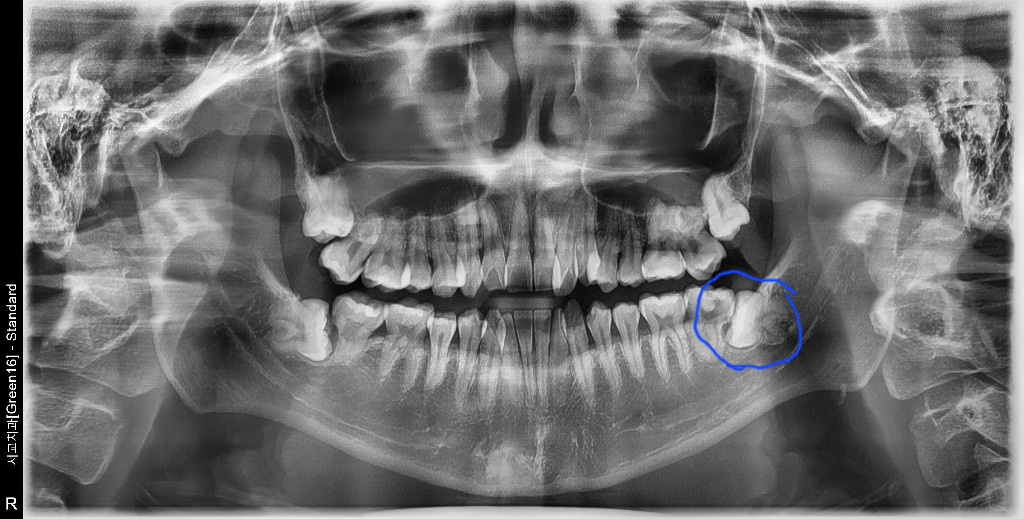

[개요]

10. 신촌세브란스 치과대학 치과보존과 박도x 교수님 진료 진행 (CT 및 파노라마 촬영)

11. 사랑니 뽑은지 4개월 밖에 되지 않았고, 발치해야할 가능성 낮게 보인다는 의견. 신경치료 약 2회(회당 5만원)하고 치아 막고(40만원 / 치아를 막는다는 건지 염증을 막는다는 건지 헷갈림) 크라운(100만원) 씌우길 권장

• 2번 째 사진